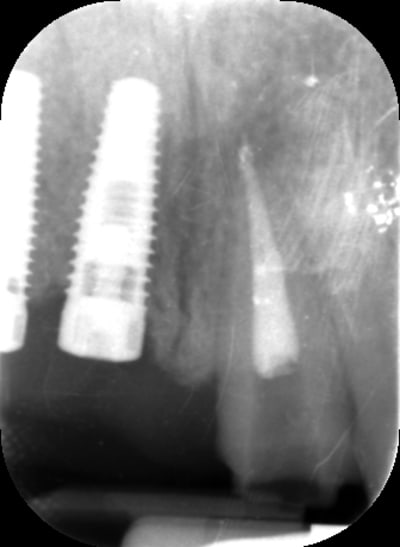

Bon voila le scann de 11-12 (pas 21-22 comme noté)

C'est vrai que j'ai à mort d'os en épaisseur.

Le manque est surtout en hauteur.

Dans tous les cas je refais 21 en même temps.

le montage guide RX laisse supposer un manque d'un mm en 12 et ok en 11. Surcomble en cj pour en éliminer au cas où avant les empreintes

Bon ben j'ai implanté avant d'avoir refait la 21. Du coup j'ai mésialé la pose de 11 pour compenser la distalisation de 21.

Au final je n'ai pas fait de greffe osseuse... et j'ai réalisé une technique de rouleau sur 11-12 mais je reste un peu court à mon goût.